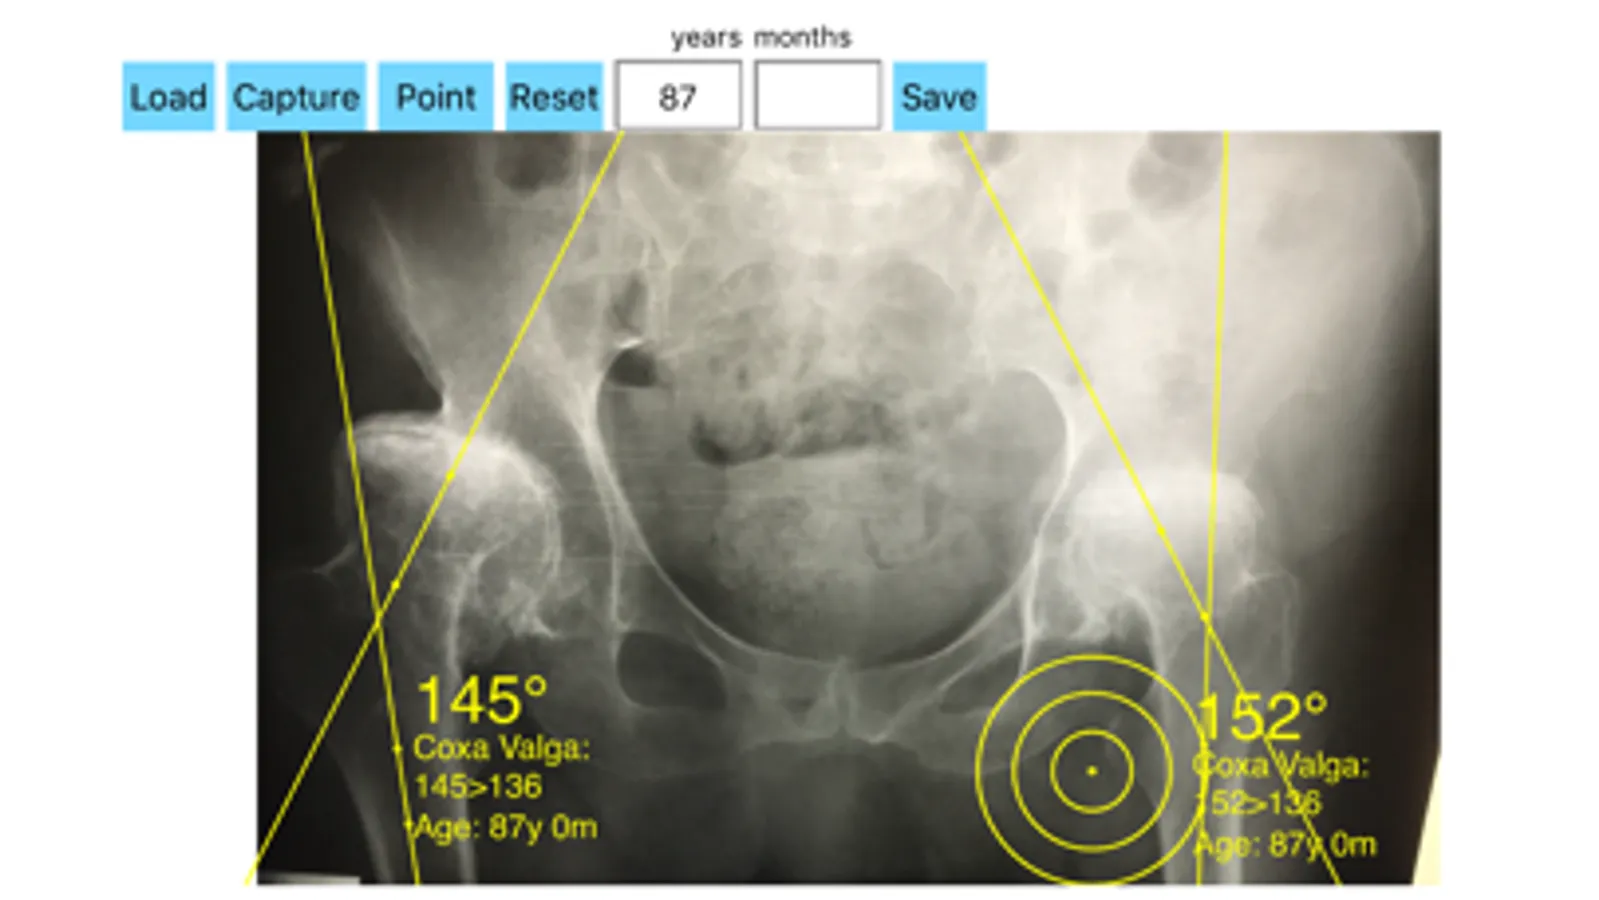

-Offers a very convenient way to determine the most accurate possibly lines in order to measure the angle. By the aid of a circular template, four points of interest are marked. The automatically formed lines drawn between points give an angle which is measured automatically by the App. The visualized results are in degrees.

By inputing the age of the patient in the App, the measured angle is compared with values from normal reference database (see reference) according the patient age. In case the measured angle is increased or decreased, the hip is valgus or varus respectively.